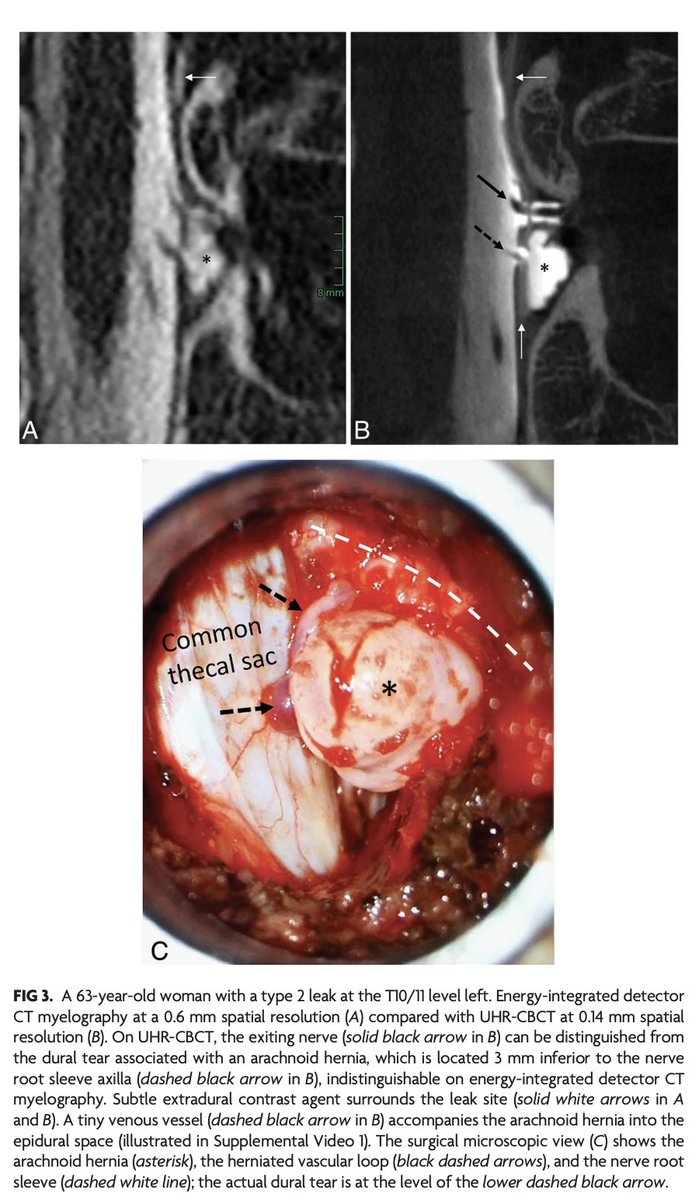

"Advanced Imaging of Type 2 Spinal CSF Leaks with Ultra-High-Resolution Conebeam CT Myelography" https://t.co/MeAXkyWHLb

@The_ASSR #CSFLeak